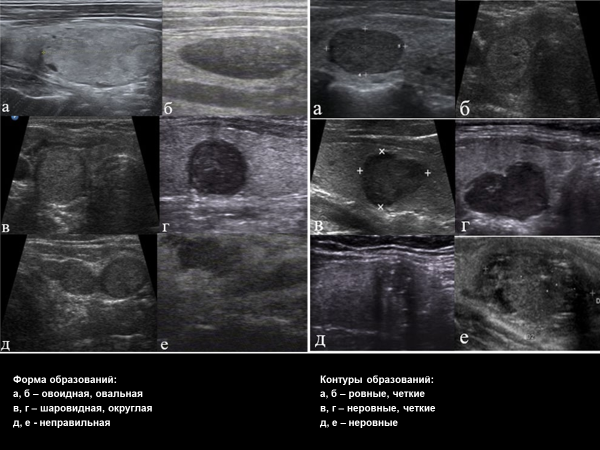

• Форма: правильная (овальная, овоидная, шаровидная)/неправильная.

• Контур: ровный/неровный (лучистый, звездчатый, бугристый, микродольчатый).

• Пространственная ориентация: горизонтальная (ширина больше высоты); вертикальная (высота больше ширины) - определяется на поперечном срезе; неопределенная или шаровидна/округлая (должна определяться как на поперечном, так и на продольном срезах).